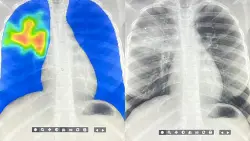

AI steps in to detect the world's deadliest infectious disease

There's a global shortage of radiologists. Now artificial intelligence is helping speed up the diagn...